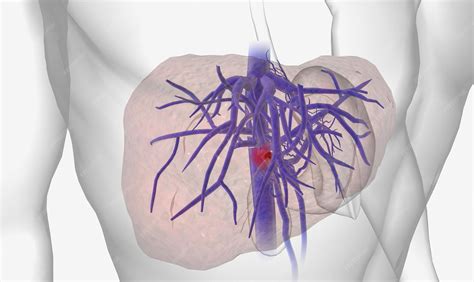

Portal Vein Thrombosis (PVT) is a serious medical condition characterized by the formation of a blood clot within the portal vein, the major vessel responsible for carrying blood from the gastrointestinal tract and spleen to the liver. When this vessel becomes blocked or narrowed by a thrombus, it can disrupt normal blood flow, potentially leading to increased pressure in the portal venous system—a condition known as portal hypertension—and severe complications if left untreated. Understanding the causes, symptoms, and treatment options for this condition is crucial for both patients and healthcare providers, as early detection significantly improves clinical outcomes.

Confirming a diagnosis of Portal Vein Thrombosis requires advanced imaging techniques to visualize the blood flow and the clot itself. Physicians will typically utilize non-invasive tools as the first line of defense.